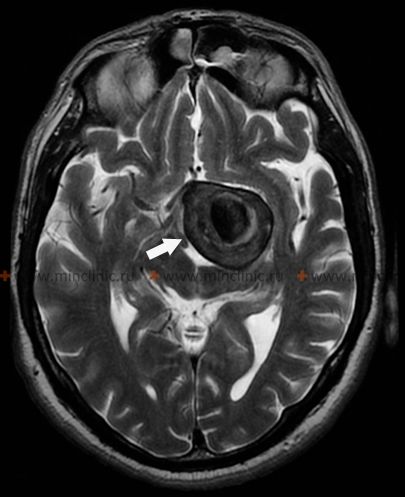

Giant intracranial aneurysms, defined conventionally as those with a maximum diameter greater than or equal to 25 mm, generally occur in the same locations along the cerebral circulation as smaller aneurysms, typically arising at vessel branching points or areas of hemodynamic stress [1, 3]. Common locations where giant cerebral aneurysms are found include the intracranial internal carotid artery (particularly at the origin of the posterior communicating artery, anterior choroidal artery, or the carotid terminus bifurcation), the middle cerebral artery (MCA) bifurcation or trifurcation, and the apex of the basilar artery [1, 3]. While rupture leading to subarachnoid hemorrhage is always a concern with any aneurysm, giant aneurysms often present with neurological symptoms primarily due to their significant mass effect – compression of adjacent cranial nerves, brainstem, or brain parenchyma – rather than solely through rupture [1, 3, 4].

Significant brain edema (swelling) can result from direct compression or potentially from altered hemodynamics related to a giant aneurysm [1]. If severe and progressive, this edema can become irreversible, leading to critical brain compression, increased intracranial pressure, herniation syndromes, and ultimately, patient death [1]. This risk of severe, life-threatening mass effect might be particularly high with certain giant aneurysms, such as those located at the middle cerebral artery bifurcation where they can compress large areas of the temporal or frontal lobes [1]. In situations with acute neurological deterioration due to mass effect from a giant aneurysm, urgent intervention (whether neurosurgical or endovascular) aimed at decompressing the aneurysm or reducing its mass may be the only viable treatment option [1, 5]. However, direct surgical clipping or endovascular treatment (coiling, flow diversion) of giant cerebral aneurysms is often technically challenging due to their size, wide necks, incorporation of vital branch origins, presence of intraluminal thrombus, and calcification of the aneurysm wall [1, 5]. Such complex interventions carry significant risks and can sometimes be complicated by issues like postoperative cerebral edema or incomplete aneurysm occlusion [1, 5].

| Giant Aneurysm (Saccular/Fusiform) | Well-defined vascular outpouching/dilatation ≥25mm. Often arises at bifurcation. May have mass effect (CN palsies, brain compression), headache, +/- rupture (SAH/ICH). | MRI: Often complex signal (flow voids, laminated thrombus). MRA/CTA shows direct connection to parent artery. DSA confirms diagnosis, details neck/flow. |